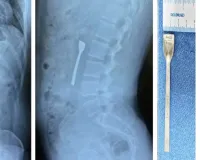

દાંતની સારવાર પણ અમેરિકામાં ખુબ જ મોંઘી છે એટલે અમેરિકામાં વસ્તા નોન રેસિડન્ટ  ઇન્ડિયન(NRI)ને જો દાંતની સારવાર કરાવવાની હોય તો ગુજરાત આવીને જ ડેન્ટિસ્ટ પાસે કરાવે છે. અમરિકામાં જો તમારે એક ચોકઠું બદલાવવાનું હોય તો ભારતીય રૂપિયામાં 3થી 3.50 લાખ રૂપિયાનો ખર્ચો થાય, જ્યારે ગુજરાતમાં 30 હજારથી 50000માં આ કામ પતી જાય. ગુજરાતીઓ પ્રસંગોમાં ગુજરાત આવતા જ હોય છે  તે વખતે ડેન્ટિસ્ટ પાસે એપોઇટમેન્ટ લઇને દાંતની સારવારા કરાવી દે છે.